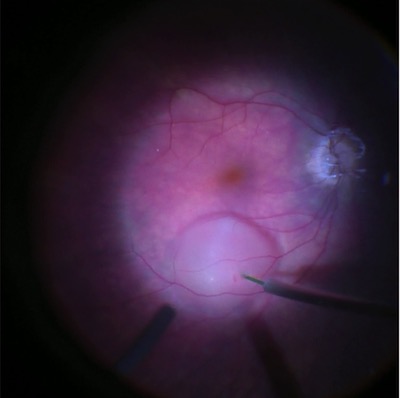

Här ser man hur läkemedlet injiceras under näthinnans gula fläck. Innan dess har glaskroppen tagits bort kirurgiskt. Foto: Gunnar Jakobsson

Luxturna består av en virusvektor som innehåller en normalfungerande kopia av RPE65-genen.

När läkemedlet injiceras i näthinnan levererar vektorn den normala genkopian till celler i näthinnan. De kan då börja producera normalt RPE65-protein, vilket gör att synen förbättras.

– Det krävs en regelrätt operation där man tar bort glaskroppen och sedan sprutar läkemedlet under näthinnan, i gula fläcken. Sedan måste patienten ligga på rygg i 24 timmar för att vätskan ska ligga kvar i gula fläcken tillräckligt länge.